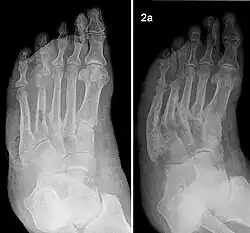

- Bildgebung: Röntgendiagnostik, Computertomographie, Kernspintomographie/Magnetresonanztomografie[11] eventuell eine Leukozytenszintigraphie, um den Verdacht auf eine Osteomyelitis auszuschließen. Eine allein auf konventionellen Röntgenbildern basierende Diagnostik wird heutzutage vom Oberlandesgericht Köln als unzureichend angesehen.[12] Das konventionelle Röntgenbild diagnostiziert geschlossene Fußfrakturen nur ungenau: übersehen werden 43 % der Metatarsalfrakturen bzw. 76 % der Tarsalfrakturen (Goldstandard: Magnetresonanztomografie, CT).[13]

Der Charcot-Fuß kann nach verschiedenen Kriterien eingeteilt werden: nach Schweregrad und Aktivitätsstadium (Einteilung nach Chantelau und Grützner), nach dem Befall der Skelettanteile (Einteilung nach Sanders und Frykberg)[14] und nach dem röntgenologischen Verlauf (Einteilung nach Eichenholtz und Levin).